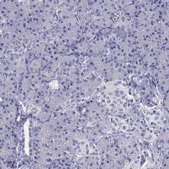

HPA072449

Anti-SCARB1

immunohistochemistry: 1:1000-1:2500